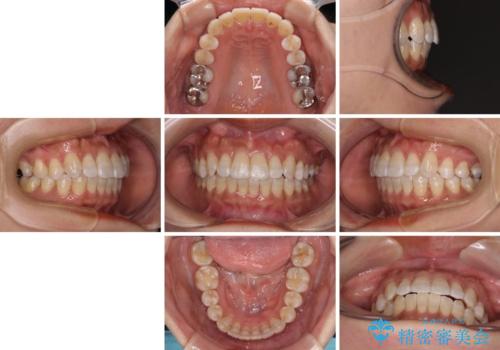

気になる八重歯 ワイヤー装置での非抜歯矯正

- 審美装置

- 2年6ヶ月

- 上顎の八重歯と全体的なデコボコを気にして来院された患者様です。

口元の突出感はなかったため非抜歯矯正での対応となりますが、八重歯を改善する際に上顎前歯が前突する可能性があったため、上顎臼歯部にアンカースクリューを使用して、歯列が前方に転位しないようにすることとしました。

また舌のトレーニングを行うことで、上顎前歯の突出予防や上下前歯に隙間ができなくなるようにしました。

ワイヤー矯正でもインビザラインでも対応可能でしたが、上顎歯列が前方位であるときには、ワイヤー矯正の方がより良い仕上がりとなる可能性が高いため、ワイヤー矯正をおすすめいたしました。